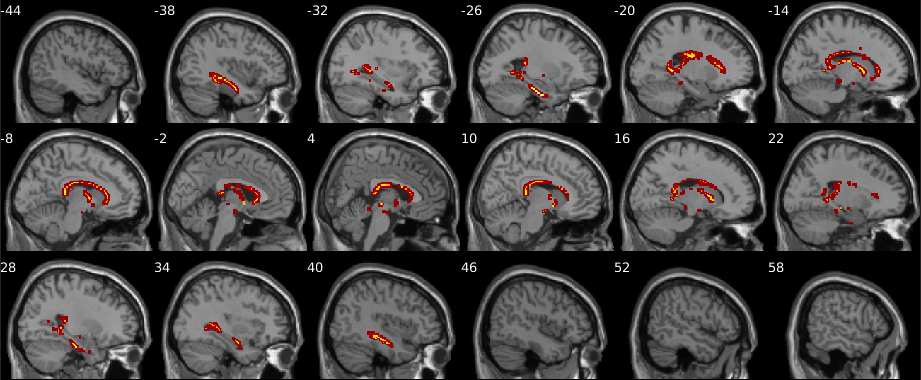

The test statistics obtained using the original data labels whose value exceed the -threshold associated to a given -value will correspond to the null hypothesis rejected. Figure 8 shows the resultant mapping between -threshold and -values for the max null distribution for a given set of hyperparameters. It is evident that the difference across methods is minimal. Moreover, Figure 8 shows that low -values (), which are the main object of interest, show the lowest differences. However, despite the low percent differences between the -values, in the larger datasets (, , and subjects) RapidPT consistently yields slightly more conservative -values near the tails of the distribution. Nonetheless, Figure 11 shows that the resampling risk between RapidPT and the two baselines remains very close to the resampling risk between both baselines. In practice, these plots show that RapidPT will reject the null hypothesis for a slightly lower number of voxels than SnPM or NaivePT.

Despite the slight difference in thresholds, the actual brain regions whose null hypotheses were rejected consistently match between both methods as shown in Figures 9 and 10. Additionally, the regions picked up by both RapidPT and SnPM in Figure 9 correspond to the Hippocampus – which is one of the primary structural brain imaging region that corresponds to the signature of cognitive decay at the onset of Alzheimer’s disease. The regions in Figure 10 contain a subset of the brain regions in Figure 9 which is expected from the thresholds shown in the right column of Figure 7.

ADNI Statistic Maps